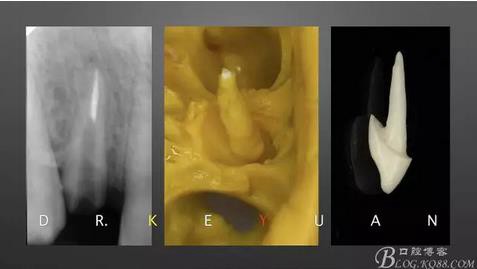

CASE 4—18歲少年,冠折后半年來(lái)診

360截圖20170120135125763.jpg

0、根管治療(千里之行始于根下)

3、取硅橡膠模型制作氧化鋯樁

360截圖20170120135210335.jpg

4、粘接氧化鋯樁